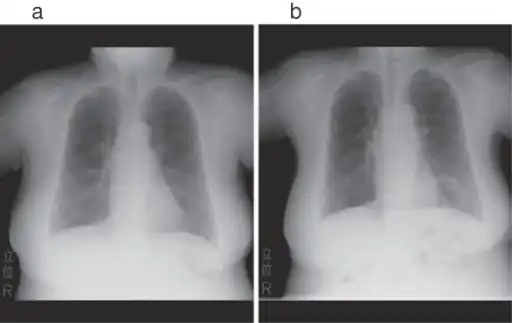

a,b)Hollow lesion in the lower left lung field was diagnosed as a lung abscess